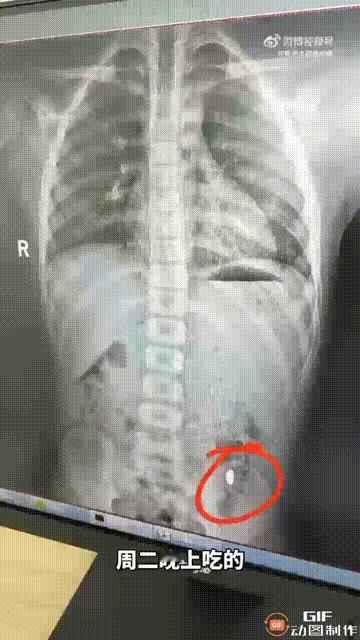

江苏苏州昆山一名女子网购了一颗重10克的金豆,拆完快递后就随手放在桌上,谁料被她的孩子发现了,还以为是吃的东西,直接就放进嘴里吞下去了,女子回来后得知傻眼了,但也不知道该怎么办,于是嘱咐孩子尽量不要在学校上厕所,因为金豆有可能会被排出来,6天后女子带孩子去医院拍片,发现金豆还在肚子里,到晚上就顺利排出来了。 网友看完这一幕,都觉得这件事真是让人哭笑不得,这名女子太大意了,重达10克的金豆,价值已经上万块,这样贵重的东西应该放好,尽量不要让孩子拿到,不过孩子误吞金豆后,女子的反应也是很搞笑了,居然让孩子不要在学校上厕所,所幸最后总算是找回了金豆,不然损失就大了。大家怎么看呢?